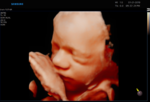

ECOGRAFÍA 5D

¡La ecografía 5D es una imagen en tres dimensiones y en tiempo real, como la 4D, pero en la que el tratamiento de las imágenes en el ordenador permite suavizar las texturas, modificar el color de la imagen y aplicar un foco de luz desde diferentes ángulos de forma que se crean luces y sombras y esto le da una imagen más real.